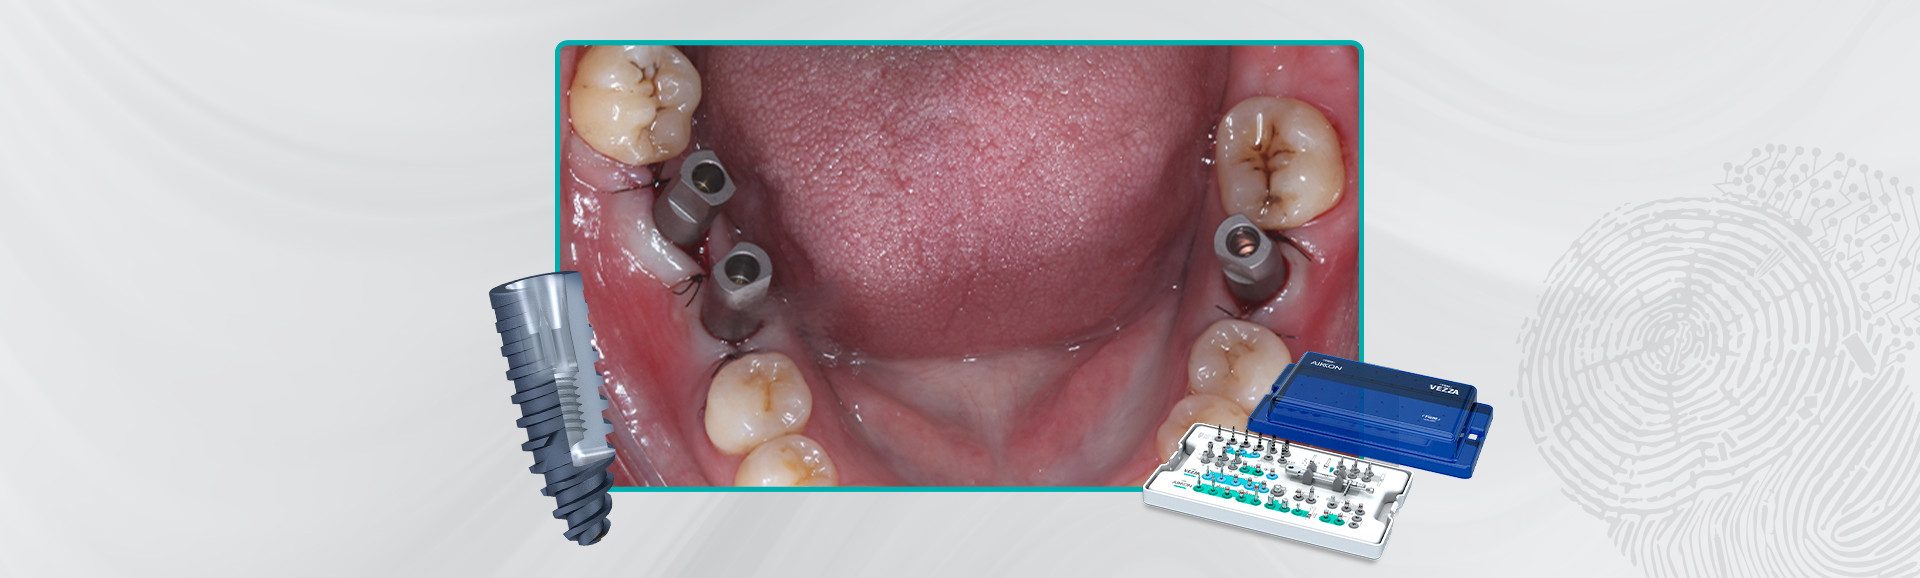

Após uma profilaxia a paciente foi submetida a anestesia local infiltrativa, retalho de espessura total e foi fresado com uma única broca com limitador de profundidade de 13 mm. Após foi conferida a posição das fresa gens com parelelizadores para posterior insta lação dos implantes. Os implantes Aikkon (3,8 × 11 mm) foram instalados 2 mm infraósseos. O torque de instalação foi de 40 N.cm (47), 60 N.cm (46) e 80 N.cm no (36). Como o torque alcançado permite a carga imediata como planejado já foram instalados os intermediários. Foi instalado o pilar Aikkon no 36 com 2,5 mm de altura de transmucoso e dois mini pilares Aikkon de altura de transmucoso 2,5 mm nos implantes 46 e 47.

14 | Intermediários Aikkon instalados e sutura realizada.

15 | Scan bodies Aikkon instalados.